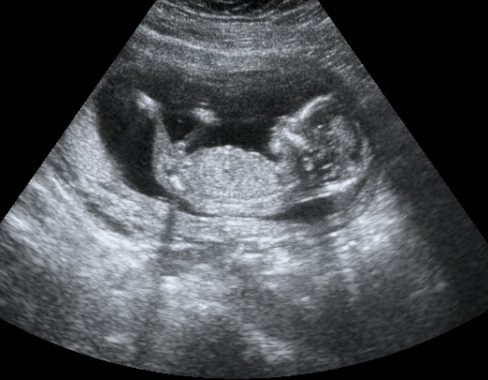

Ahogy ígértem, hoztam a képeket. Igaz Ti idősebbek vagytok a képeken, mert Boti a képeken 14+6 hetes, Ti meg ugye már 17+3 :)

Dodó Pocaklakó Kép

Boti

Kép

Dodó Pocaklakó

Na mazsolázzunk... :D